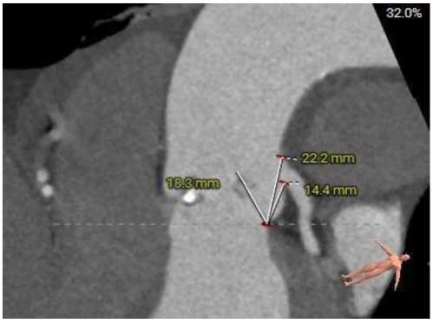

三叶式主动脉瓣,中度钙化,钙化主要分布于瓣叶附着缘及对合缘,钙化分布不均,左冠窦相对较重,右窦和无窦瓣叶对合缘处存在增厚及钙化粘连;

双侧冠脉开口高度可,左冠切线角度测量瓣叶大于LCA开口下缘到根部距离;

瓦氏窦内径尚可、窦管交界内径可、升主动脉内径可;